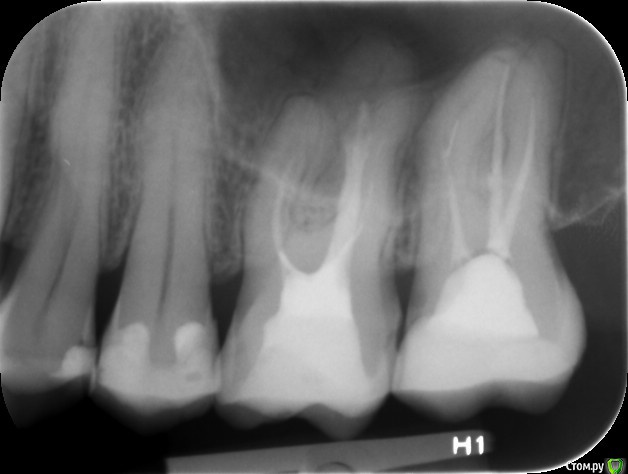

Pofigdym Опубликовано 17 октября, 2017 Поделиться Опубликовано 17 октября, 2017 (изменено) Доброго времени суток. Что то разболелось в верхней левой челюсти. По ощущениям думал на 25. На данный момент нахожусь в Нидерландах, пошел тут к стоматологу. Сделали снимок, на снимке стоматолог увидел воспаление под 26. Сказал, что скорей всего из за некачественной пломбировки каналов в 26. С антибиотиками сказал подождать, попросил связаться с клиникой где зубы депульпировали и попросить снимки первоначальной ситуации с зубом, что бы отценить, воспаление прогрессирует или уменьшается в сравнении с сегодняшним снимком.Интересует мнение уважаемых стоматологов этого форума, так ли все плохо с заполнением каналов? Заранее спасибо. Снимок: https://hostingkartinok.com/show-image.php?id=bdb3b5bb3d68a481103bd4b0b6181a0e Изменено 17 октября, 2017 пользователем Pofigdym Ссылка на комментарий

red_butler Опубликовано 17 октября, 2017 Поделиться Опубликовано 17 октября, 2017 Шестой и седьмой зубы нужно повторно лечить каналы.Опишите Ваши жалобы, характер боли, есть ли её локализация, провоцирующие факторы... 1 Ссылка на комментарий

Pofigdym Опубликовано 18 октября, 2017 Автор Поделиться Опубликовано 18 октября, 2017 На 7 сам вижу что гуттаперча то ли загнулась то ли зацепилась за что то а в 6 понять не могу, вроде все пройдены и заполненв. Воспаление вроде как идёт от не до конца заполненного канала у 7? Стоматолог в Латвии, тот что делал, согласен, что надо перелечить 7 но 6 оставить в покое и пить антибиотики. Говорит, у обоих зубов кальцификация каналов и кривизна, очень трудно проходить и не факт, что эндодонтолог с микроскопом поможет. Стоматолог в Нидерландах хочет 6 и 7 перелечить и антибиотики амоксицилл. Возможно ли что каналы непроходимы? Ссылка на комментарий

Stomart Опубликовано 18 октября, 2017 Поделиться Опубликовано 18 октября, 2017 На 7 сам вижу что гуттаперча то ли загнулась то ли зацепилась за что то...Это ступень в канале и похоже на обломок инструмента. Ссылка на комментарий

DmitrySH Опубликовано 18 октября, 2017 Поделиться Опубликовано 18 октября, 2017 а в 6 понять не могу, вроде все пройдены и заполненв Нет, не пройдены. на 2/3 только На 7 сам вижу что гуттаперча то ли загнулась то ли зацепилась за что то Фрагмент инструмента, видимо пытались обойти и получили ступень. Но это все не очень глубоко, с микроскопом вполне решаемо Ссылка на комментарий

Marika Опубликовано 18 октября, 2017 Поделиться Опубликовано 18 октября, 2017 В 6м зубе не найден 4й канал, он то и может давать такую реакцию. Ссылка на комментарий